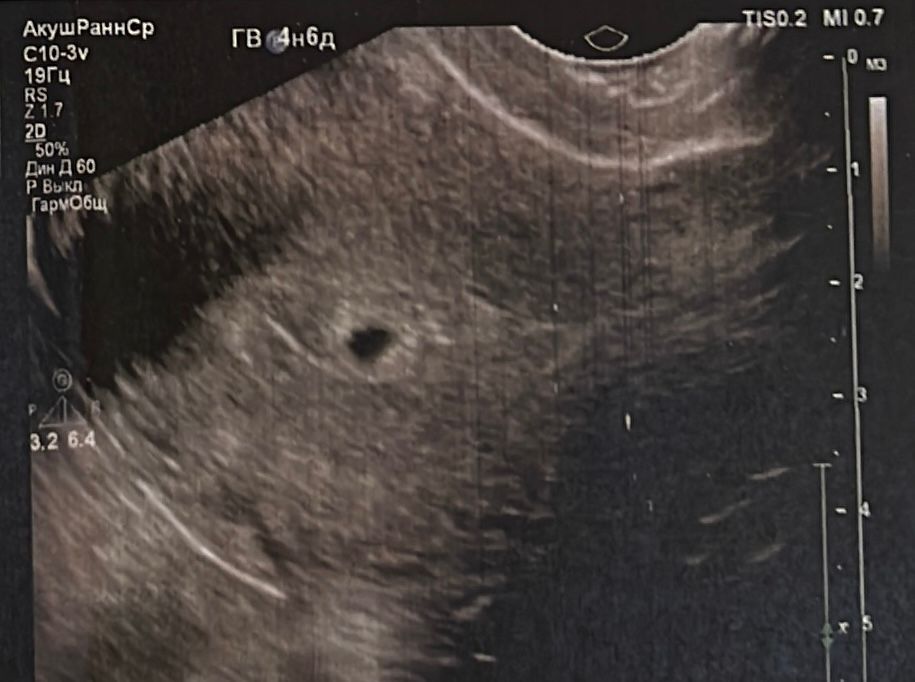

6-я неделя)